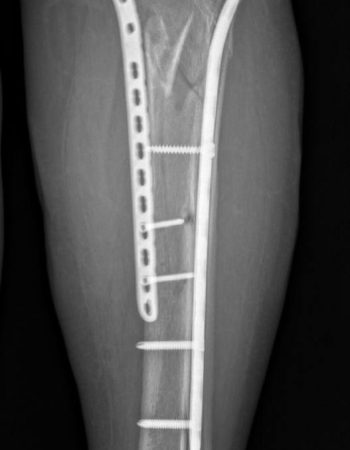

Післяопераційний період проходив без ускладнень і на 10 день після поступлення було проведено наступне етапне оперативне втручання: відкрита репозиція, металоостеосинтез пластинами.

Пацієнтка якісно провела реабілітацію і вже зараз починає навантажувати травмовану кінцівку, щоб згодом повернутися на роботу!